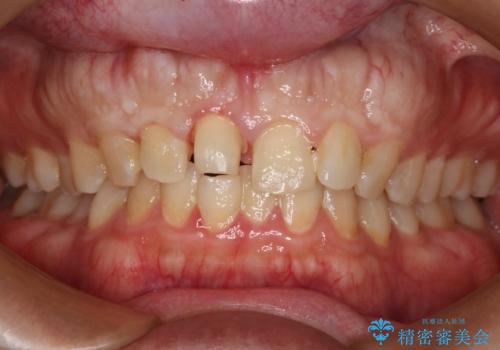

- 上の前歯の一部が欠けてしまったので治療を希望し来院された患者様です。

破折状態から歯髄(歯の神経)は保存できると判断し、クラウンでの治療を計画しました。